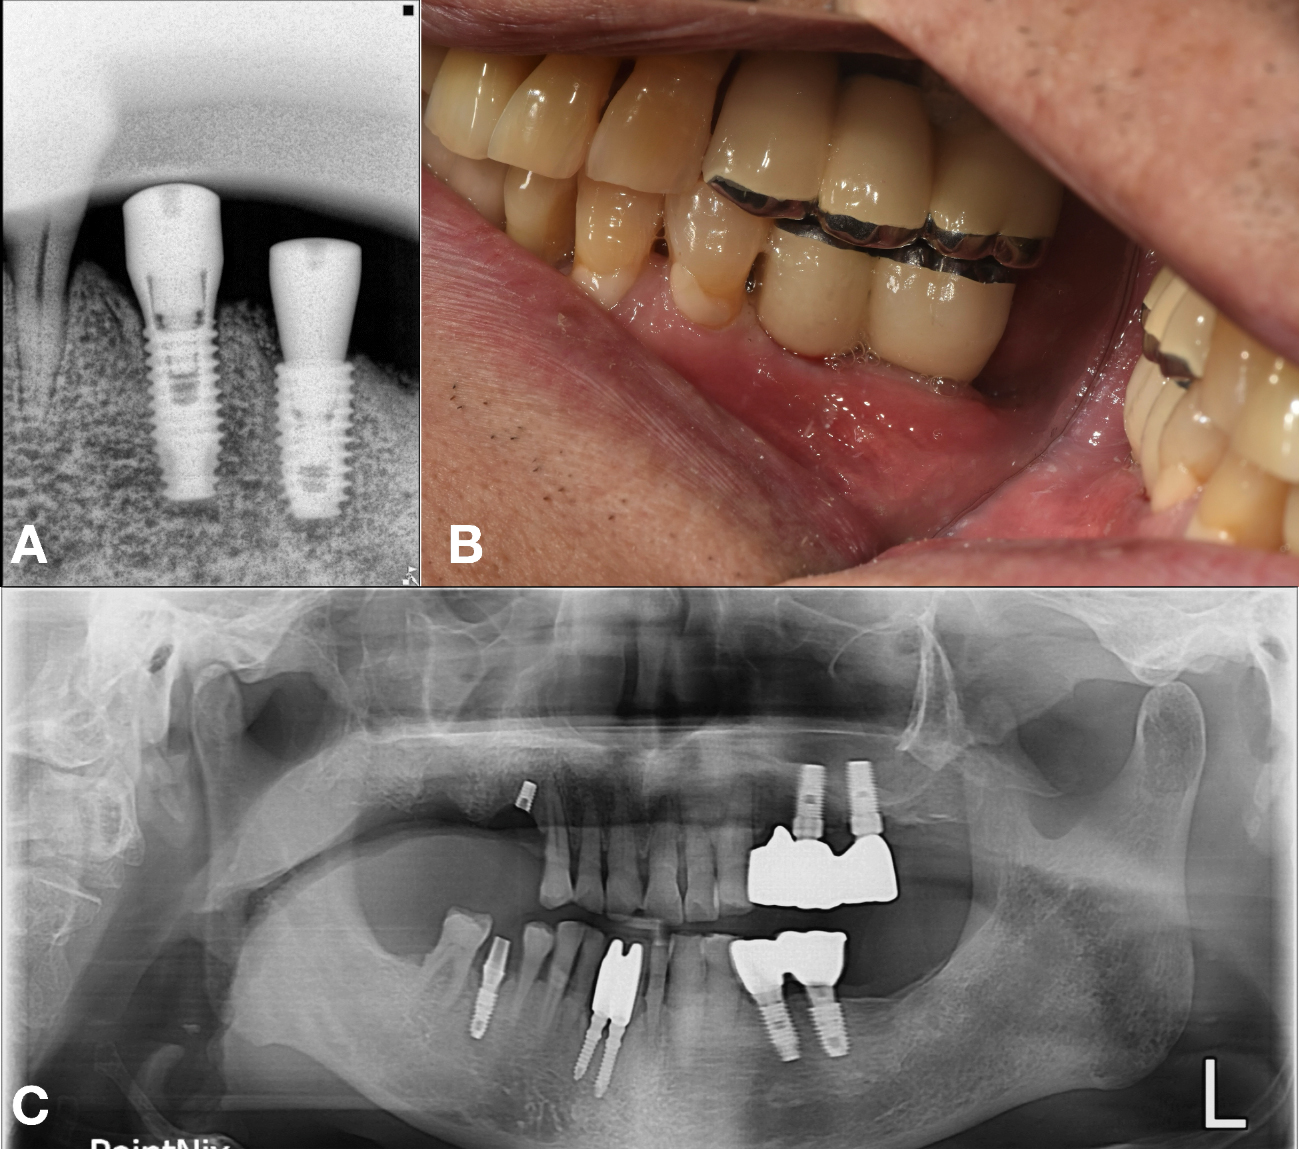

A 69-year-old male presented with discomfort in the left mandibular molar region. Tooth #36 was deemed hopeless and subsequently extracted, whereas the adjacent #35 implant exhibited a fractured crown on an existing undocumented fixture.6, 7 Two months after a GBR with a FDBA at site #36, a new implant (TSIII, 4.5 mm diameter and 8.5 mm length; Osstem Implant) was placed with an initial torque of 35 Ncm. A healing abutment (5 mm diameter, and 7 mm height) was simultaneously placed. As the implant at site #35 remained undocumented, the KAOMI team again was consulted. The fixture was identified as SS-2 (SS-2; Osstem Implant) (Fig. 7).

An appropriate stock abutment for fixture (#35) was procured, enabling reuse of the existing implant for patient comfort and reduced surgical morbidity. The restoration was completed based on the information provided by the implant finder service (Fig. 8A and 8B).

At the 6 year follow-up, the implants on the mandibular left side remained functional and stable. However, the patient experienced implant fracture in the maxillary right quadrant, possibly due related parafunctional activity such as bruxism (Fig. 8C).8